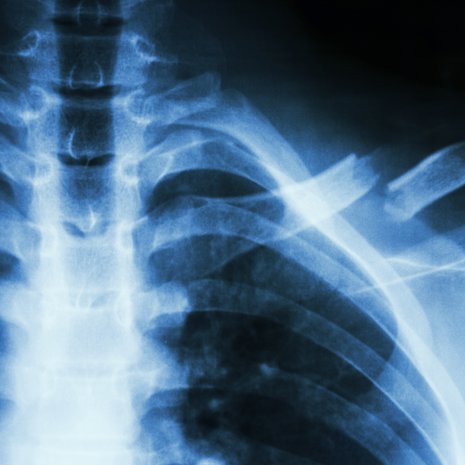

Ehdottomasti! Osteoporoosi antaa ensimerkkinsä usein vasta murtuman sattuessa. Kyse voi olla osteoporoottisesta murtumasta varsinkin silloin, jos kaatuminen kipeyttää lonkan, lantion, lannerangan, olan tai ranteen.

Osteoporoosi löytyy DXA-luuntiheysmittauksessa. Mittauksia tehdään myös yksityisesti, joten voit hakeutua sellaiseen varmuuden vuoksi.